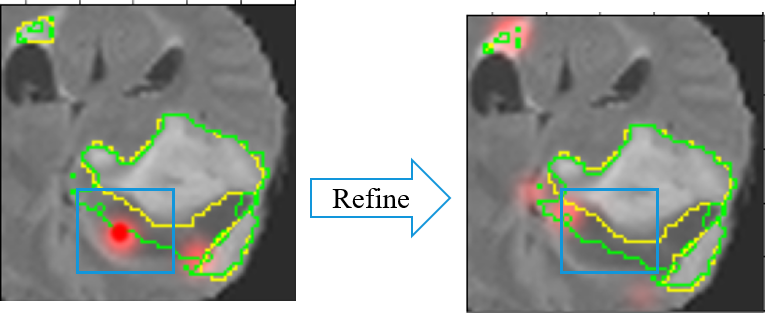

3.6 Simulated Label Generation

Refer to caption

Figure 6: The illustration of simulated label generation. The simulated label generation mechanism utilizes the confidence map and the action map to generate the simulated label. The confidence map is used to calibrate the action, and the direction of the calibrated action is the simulated label of each voxel.

In medical imaging, the unlabeled data is much more than labeled data due to difficulties in labeling medical images. To address this lack of annotations, the proposed algorithm leverages the action confidence not only to improve the utilization efficiency of hint information but also to generate a simulated label, shown in Figure 6, for unlabeled data. We define the simulated label as follow:

y^(t)={1 if a(t)c(t)==1,0 otherwise .\hat{y}^{(t)}=\left\{\begin{array}[]{ll}1&\text{ if }a^{(t)}\oplus c^{(t)}==1,\\ 0&\text{ otherwise }.\end{array}\right. (12)

The y^(t)superscript^𝑦𝑡\hat{y}^{(t)} is the simulated voxel-level label generated from the confidence map and detailed illustration is shown in Figure 6. Based on this mechanism, this study considers using these unlabeled data to assist in training the segmentation network. Specifically, this study divides the dataset into two parts during the training stage: the first part contains voxel-level annotation information, and the second part contains only hint information during training. The labeled data is trained as above, while the unlabeled data is trained with the simulated label. During the training stage, the backward of gradients will be masked: